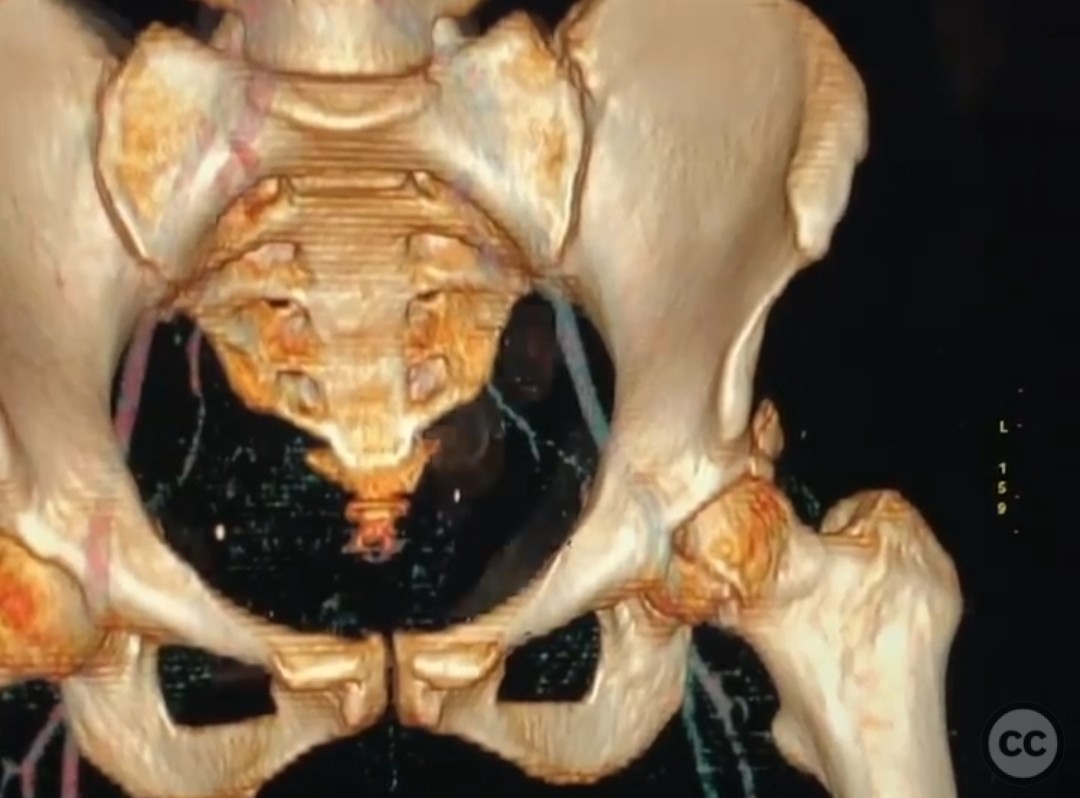

Clinical and radiological findings:  A 33-year-old female involved in a motor vehicle collision presented with a posterior hip dislocation accompanied by a comminuted supra-foveal femoral head fracture, a cranial peripheral posterior wall fracture, and a non-displaced femoral neck fracture. The injury is associated with a risk of sciatic nerve palsy and avascular necrosis (AVN).

Planning remarks:  The preoperative plan involved a Gibson approach with a trigastric slide osteotomy for anterior dislocation to address the femoral head fracture. The intention was to reconstruct the femoral head using a femoral head allograft due to a 20% pie slice defect. The posterior wall was to be addressed through capsulolabral repair with suture anchors and spring plates.